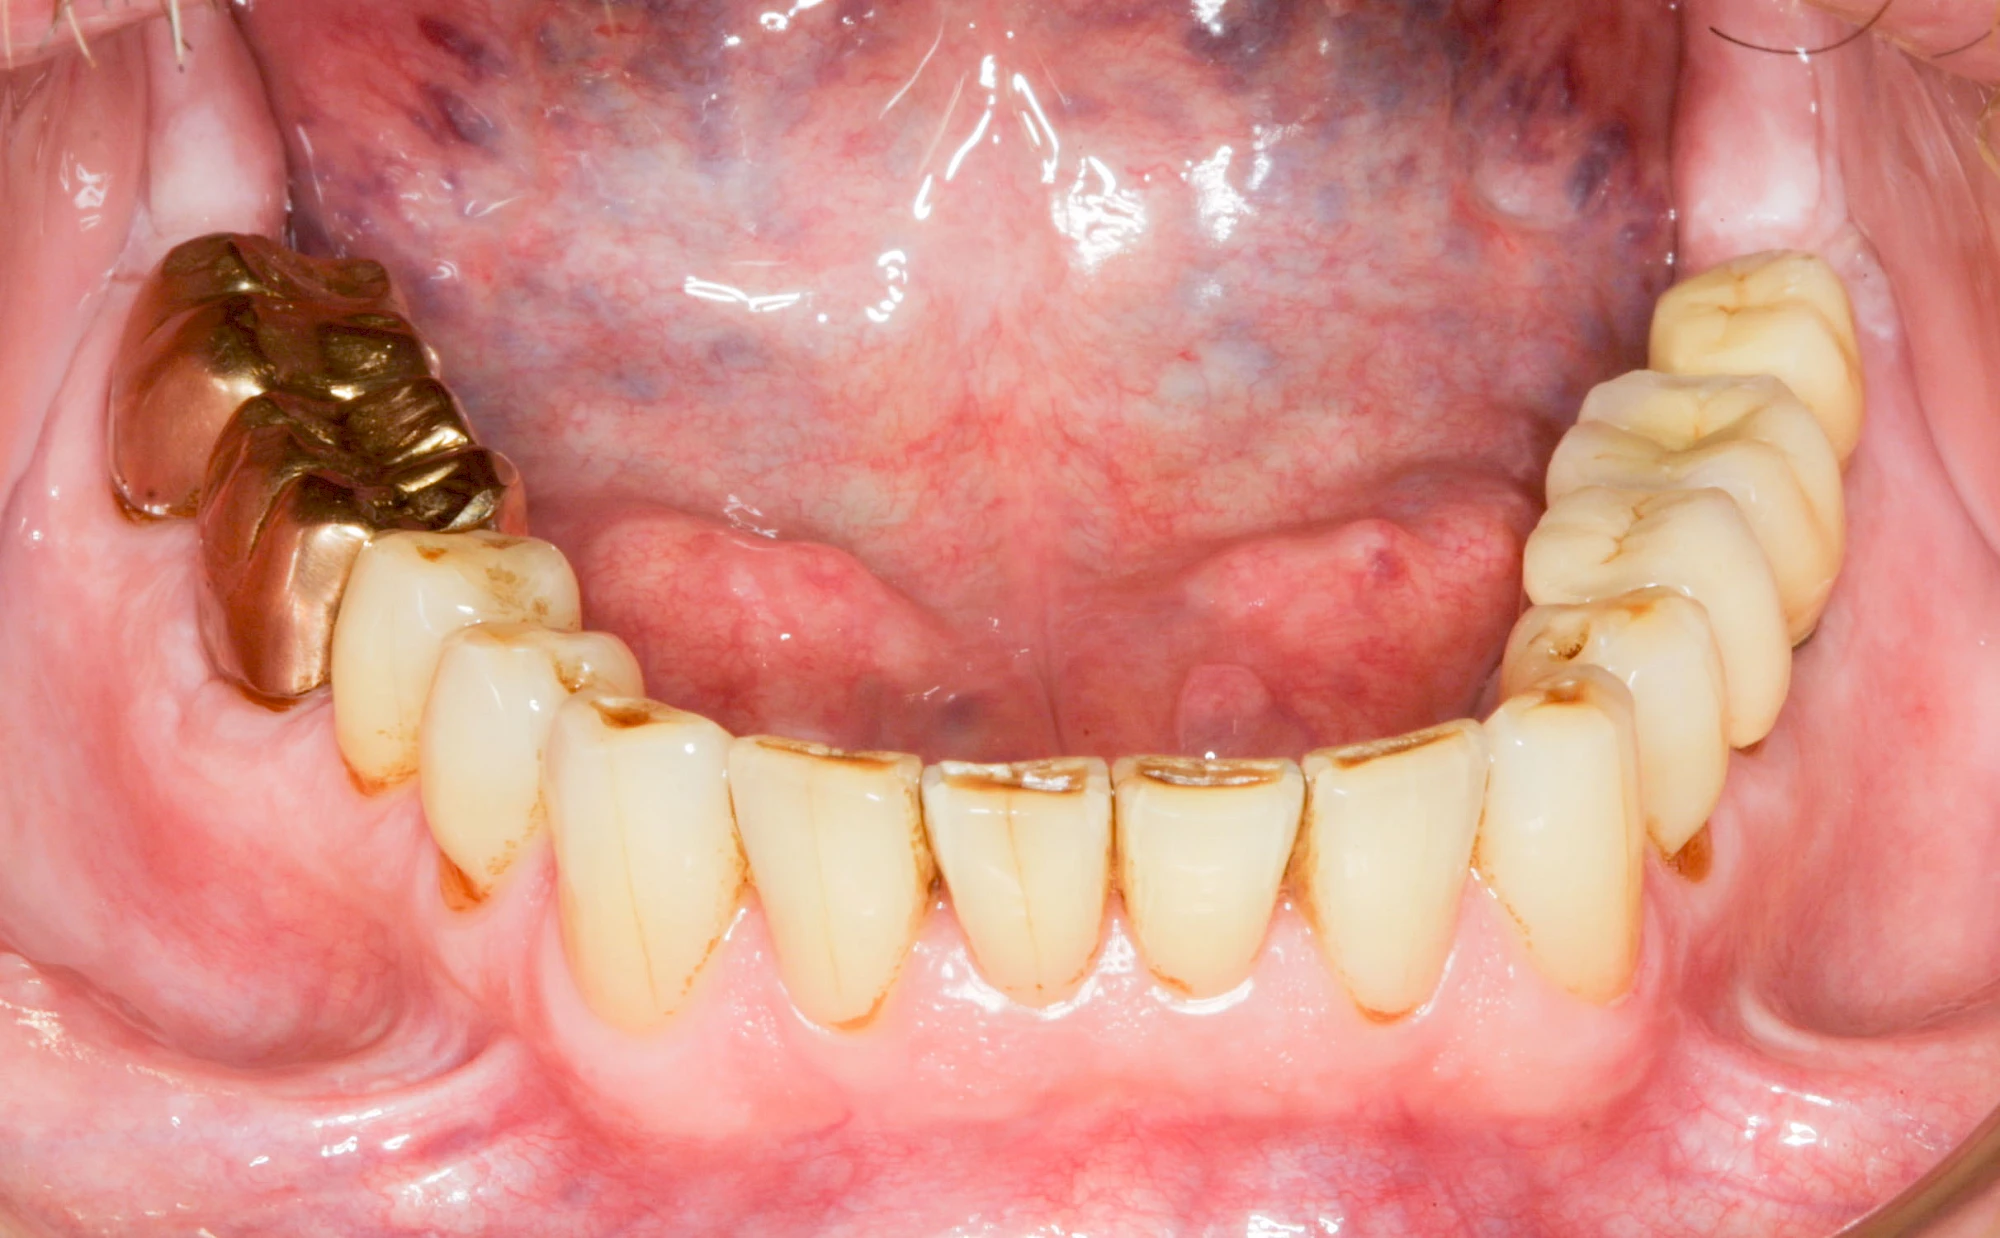

Bei herausnehmbaren Prothesen werden Implantate eingesetzt, um den Halt und den Tragekomfort der Prothesen zu verbessern. Dazu kommen verschiedene Verbindungselemente zum Einsatz:

- Teleskope

- Kugelköpfe

- Tellerförmige Lokatoren

- Stege

- Magnete (selten)

Neben rein implantat-getragenen zahnärztlichen Versorgungen werden bei herausnehmbaren Prothesen Implantate auch in Sinne einer "strategischen Pfeilervermehrung" ergänzend zu eigenen Zähnen zur Verankerung eines Zahnersatzes genutzt.